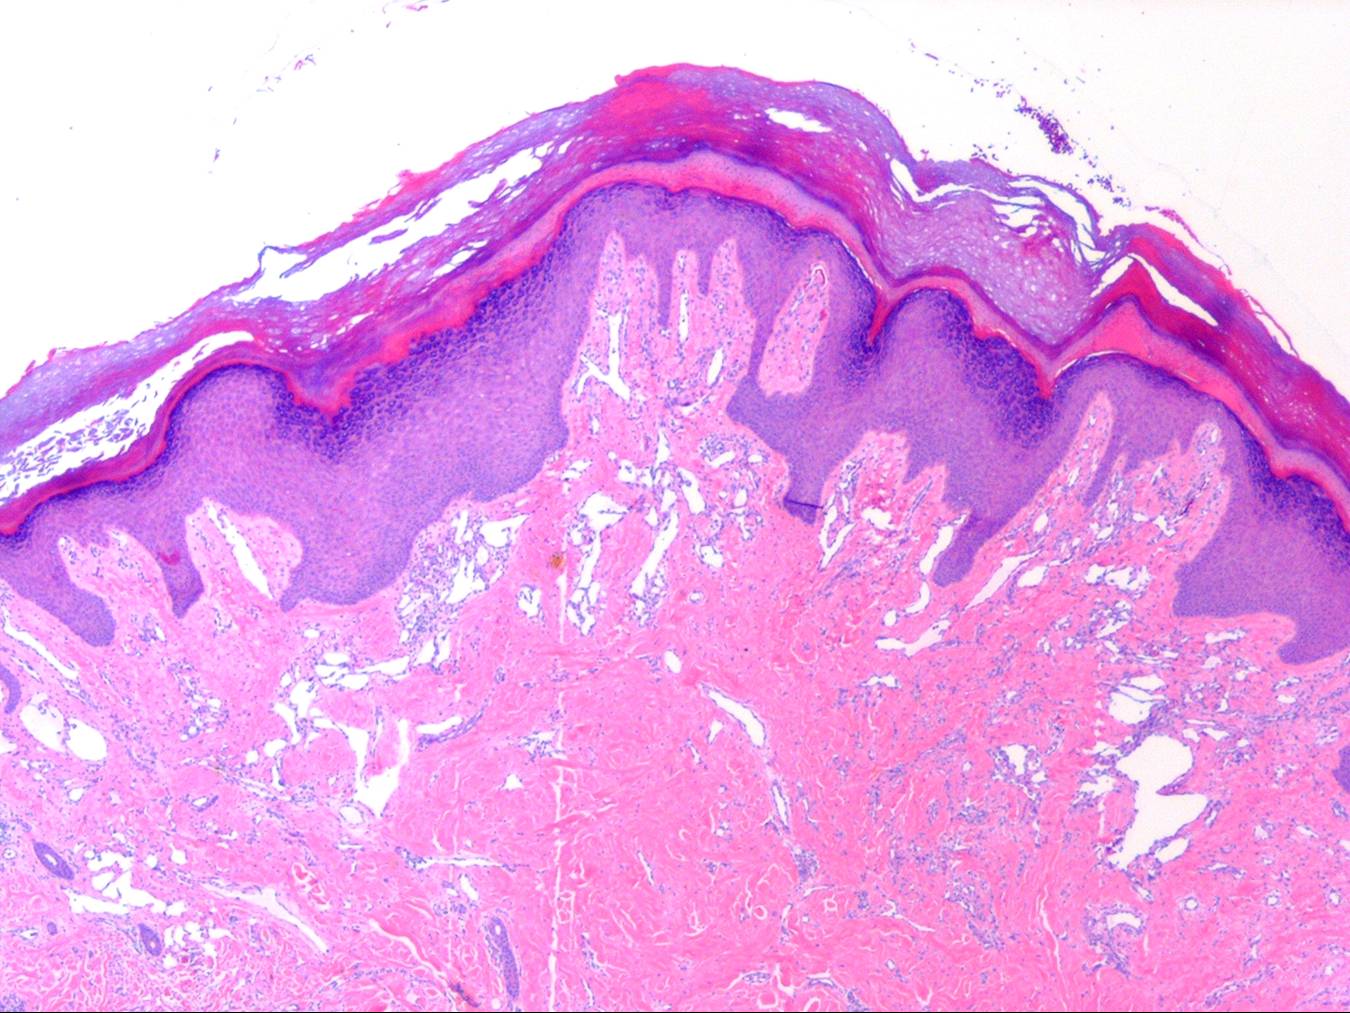

Acquired progressive lymphangioma =الورم الوعائي اللمفاوي المترقي المكتسب